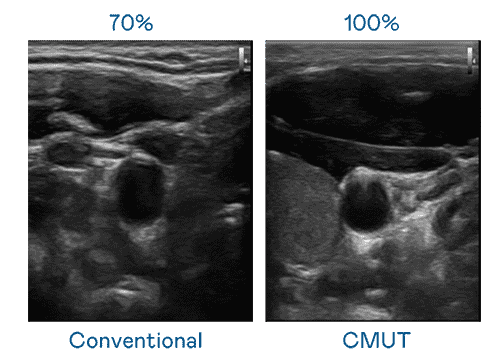

CMUT 技术是一种用电容式微机电元件来产生超音波讯号的技术。。。。与传统 PZT 压电式技术相比,,CMUT 频宽增加 30%,,,,更宽频的超音波讯号让影像解析度大幅提升,,,是实现高影像品质医疗超音波扫描、、、、促进精准医疗发展的关键技术。。。。

大频宽带来超清晰影像

超音波影像的解析度高低,,,首先取决于探头能发出的讯号频宽。。。2121非凡 CMUT 可提供高清晰的超音波讯号,,提供高频宽、、、高灵敏度、、影像纹理细节更高的超音波影像,,协助医护人员缩短影像判读时间及利用精准的医疗影像进行诊断。。。。